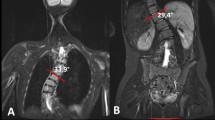

The radiographs were analyzed by the IDS 7-PACS®-System (Sectra, Linköping, Sweden). In all available radiographs (FSR, PPR, and the CTS) the Cobb angle of the main curve and of the upper and lower minor curve was measured. Furthermore, we measured the segmental Cobb angle of the intervertebral space under the lowest vertebra of the main curve (ISE) and the angle of the first flexible intervertebral space below the main curve (FFI). Measurement of Cobb angle in the CTS is demonstrated in (Fig. 1). Measurement was performed in coronal reconstructions of the CT scan. End vertebras were identified in the FSR. The angle between the superior endplate of the cranial end vertebra and the horizontal plane and the angle between the inferior endplate of the caudal end vertebra and the horizontal plane was measured. These two angles were added to obtain the Cobb angle of the according curve (Fig. 1).

Measurement of Cobb Angle in a CTS. a Coronal reconstruction of a CT scan of the spine. The superior endplate of the cranial end vertebra of the according curve is depicted. End vertebra were identified in the FSR. The angle between the superior endplate of the cranial end vertebra and the horizontal plane was 18,4°. b Coronal reconstruction of a CT scan of the spine. The inferior endplate of the caudal end vertebra of the according curve is depicted. End vertebra were identified in the FSR. The angle between the inferior endplate of the caudal end vertebra and the horizontal plane was measured with 21,2 degrees. Summation of these two angles (18,4 + 21,2) gives us a Cobb angle of 39,6 degree for the complete thoracic deformity